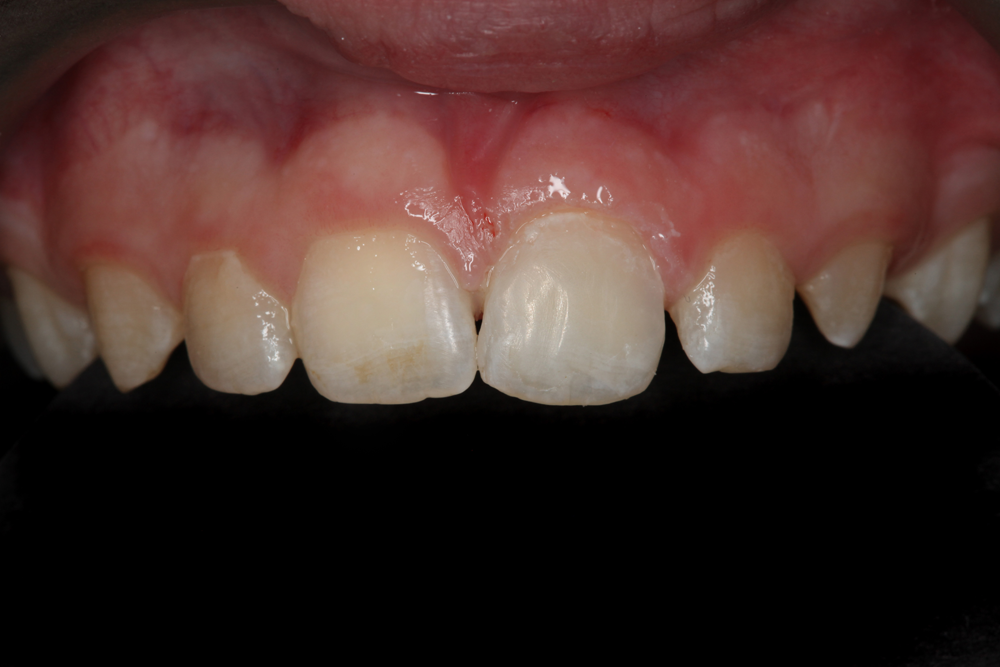

As demonstrated in this article, teeth to which a fractured tooth segment has been reattached can be predictably and esthetically restored with minimally invasive techniques when proper adhesive protocol and advanced direct restorative materials are used (Fig. 7). Essential to achieving these objectives is selecting truly universal materials on a case-by-case basis that can be placed easily and precisely, demonstrate predictable bond strengths and facilitate replication of life-like esthetics, particularly blending with adjacent natural teeth. In this case, the combination of G-Premio BOND, G-CEM LinkForce and G-ænial Sculpt helped to reduce procedural challenges, increase efficiency and enhance clinical efficacy.

Fig. 7